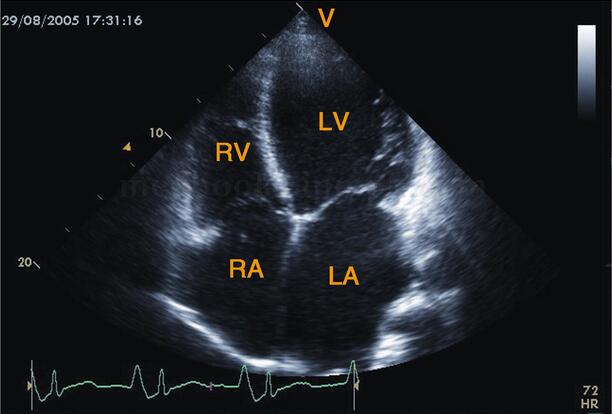

图2‐1‐182 心尖四腔心切面图心脏各心腔均扩大,以左室、左房扩大为著

超声描述 全心扩大,以左心为主,左室舒张末期内径78.5mm;主动脉振幅减低,呈充盈不足表现;二尖瓣开放相对小,左室呈“大心腔,小瓣口”,E峰至室间隔距离(EPSS)增大为25﹒6cm;室壁运动弥漫性减弱,左室射血分数34.5%;二尖瓣口E峰明显大于A,呈限制性充盈,二、三尖瓣中度反流;少量心包积液。

超声诊断 符合扩张型心肌病声像图改变,左室双期功能减低,二、三尖瓣中度反流(相对),少量心包积液。

(1)四个房室腔均明显增大,以左室、左房为著。侵犯右心的心肌病表现右心扩大为主(图2‐1‐184)。